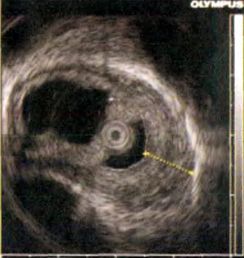

病例资料 患者,男,54岁,因“进食后腹胀伴暖气、返酸1月余,进食哽咽感2周”入院。起病以来,午后发热,在37.5℃~38.5℃之间波动,无腹痛、腹泻、胸闷及胸痛等表现。当地医院就诊,胸部CT平扫未见异常:胃镜提示:食管距中切牙36 cm至贲门齿状线可见一 1.0 cm×2.0 cm溃疡型肿块,表面污秽,呈结节状,活检质脆,易出血,考虑食管癌可能:病理示食管黏膜慢性炎性反应伴少量炎性坏死渗出物。患者至上海某医院就诊,再次行胃镜检查.提示距中切牙35~39 cm,溃疡新生物,病理提示:食管鳞形上皮及炎性肉芽肿组织。近2周来,患者出现进食后哽咽感,以进固体食物时明显。至我院就诊,行胸部增强CT示,食管下段管壁增厚,符合恶性肿瘤改变;胃镜示,食管距中切牙35~39 cm前壁左侧见黏膜隆起,表面高低不平,溃疡形成,质硬,易出血,见图1。超声胃镜示,局部食管壁各层结构消失,考虑食管恶性肿瘤,见图2。但病理示:食管鳞形上皮轻度增生,并见炎性肉芽组织和炎性渗出坏死物,符合炎性溃疡,见图3。遂行肠镜检查.提示回盲部溃疡,肠镜病理示炎性肉芽组织和炎性渗出坏死物,符合炎性溃疡,灶性区似有裂隙性溃疡,符合CD。综合考虑患者病史及各种辅助检查,诊断为:食管CD。

图2 超声内镜示食管全层病变

食管造影、CT、胃镜、超声胃镜是食管疾病常用的检查手段。食管CD造影可显示溃疡,狭窄,息肉或瘘管形成。胃镜下也表现多样,常见口腔溃疡、食管浅表糜烂、狭窄以及后期的纵形或横形溃疡形成和黏膜下层高度增生造成的鹅卵石样改变.可能同时伴有食管黏膜的充血、炎性反应、组织易碎、结节性增厚和炎性肿块的形成等。该病变80%位于食管下段,15%同时位于中段和下段.3%累及全段食管。超声内镜可见食管病变部位结构、层次破坏。典型的病理组织学特征是非干酪坏死性肉芽肿形成、黏膜下层增厚和淋巴细胞聚集等,但由于CD常累及食管全层,仅仅通过内镜在黏膜取材,获得典型病理的可能性只有7%~9%。本组中仅3例发现典型的非干酪坏死性肉芽肿,故病理往往只能作为排除其他疾病的依据。